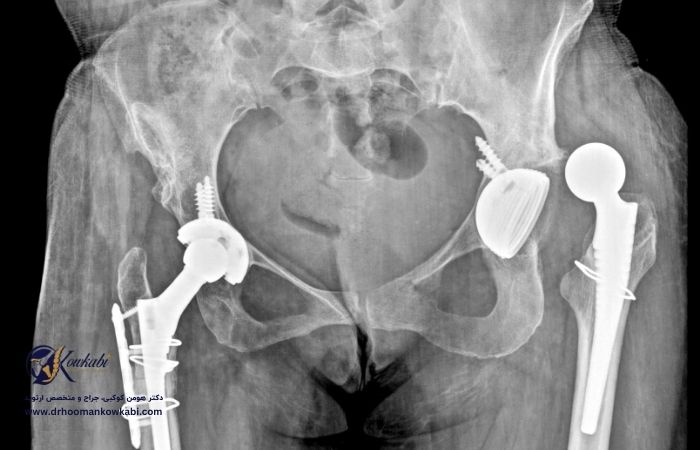

در جراحی تعویض کامل لگن (که به آن آرتروپلاستی کامل هیپ نیز گفته می شود)، استخوان و غضروف آسیب دیده برداشته شده و با اجزای پروتز جایگزین می شود. سر استخوان ران آسیب دیده برداشته می شود و با یک ساقه فلزی که در مرکز توخالی استخوان ران قرار می گیرد، جایگزین می شود.

ممکن است نیاز به تعویض مفصل ران (آرتروپلاستی مفصل ران) داشته باشید. جراح لگن شما را با ایمپلنت مصنوعی (پروتز) جایگزین می کند. اگر درد و سایر علائم در لگن بر توانایی ایستادن، راه رفتن و حرکت شما تأثیر بگذارد، ممکن است پزشک شما تعویض مفصل ران را توصیه کند.